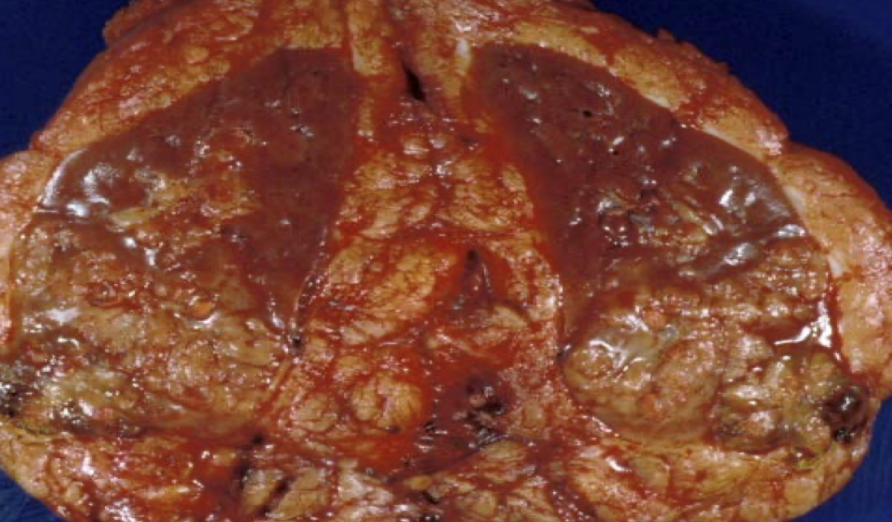

oncocytoma

arises from intercalated cells of CD

oncocytoma

numerous mitochondria = granular eosinophilic cytoplasm

oncocytoma

mahogany brown with central scar